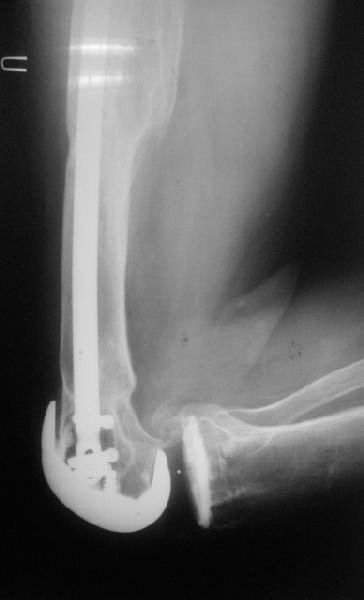

Видимо, самое "модное" на сегодня - малоинвазивный остеосинтез пластиной с угловой стабильностью. Распространенный вариант и закрытый интромедуллярный остеосинтез ретроградно. Хотя у нас было бы сделано антеградно - лешево и сердито, действительно малоинвазивно, в сустав не надо влезать. Нет риска прорезания порозной кости с миграцией в сустав, что возможно при ретроградном - гвоздь вводится через вырез в бедреннм компоненте, туда же может и вывалиться. А антеградный - упрется в протез. Как раз вчера заходил больной через полтора года после такой операции. Снимки в приложении.

на снимке признаки loosening и тибиального и феморального компонентов я думаю нужна ревизия если нет возможностей то артродез и конечно исключить инфекцию . успехов .

Мне представляется следующее: Если дистальный отдел бедра расколот и в сагиттальной и во фронтальной плоскостях, как видно на рентгенограммах, и при этом есть смещение отломков относительно друг друга и бедренного компонента эндоаротеза, разве от может оставаться стабильным? В случае отсутствия проблем с тибиальным компонентом, можно было бы надеяться только на остеосинтез и стабилизацию, но если предполагается ревизия в ближайшие месяцы/год, то не лучше ли за один раз решить несколько проблем?